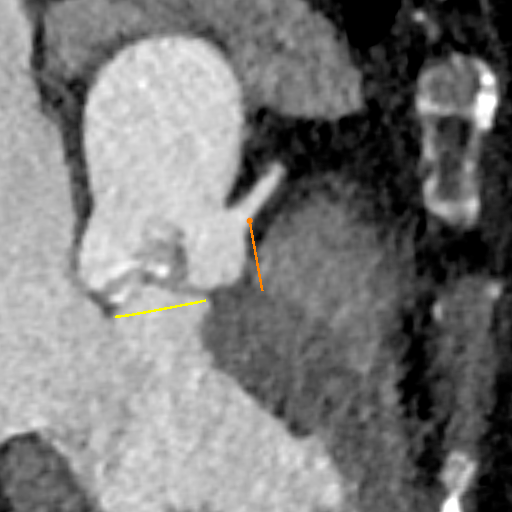

术中操作

球囊预扩

瓣膜定位

经评估后植入左主干烟囱支架